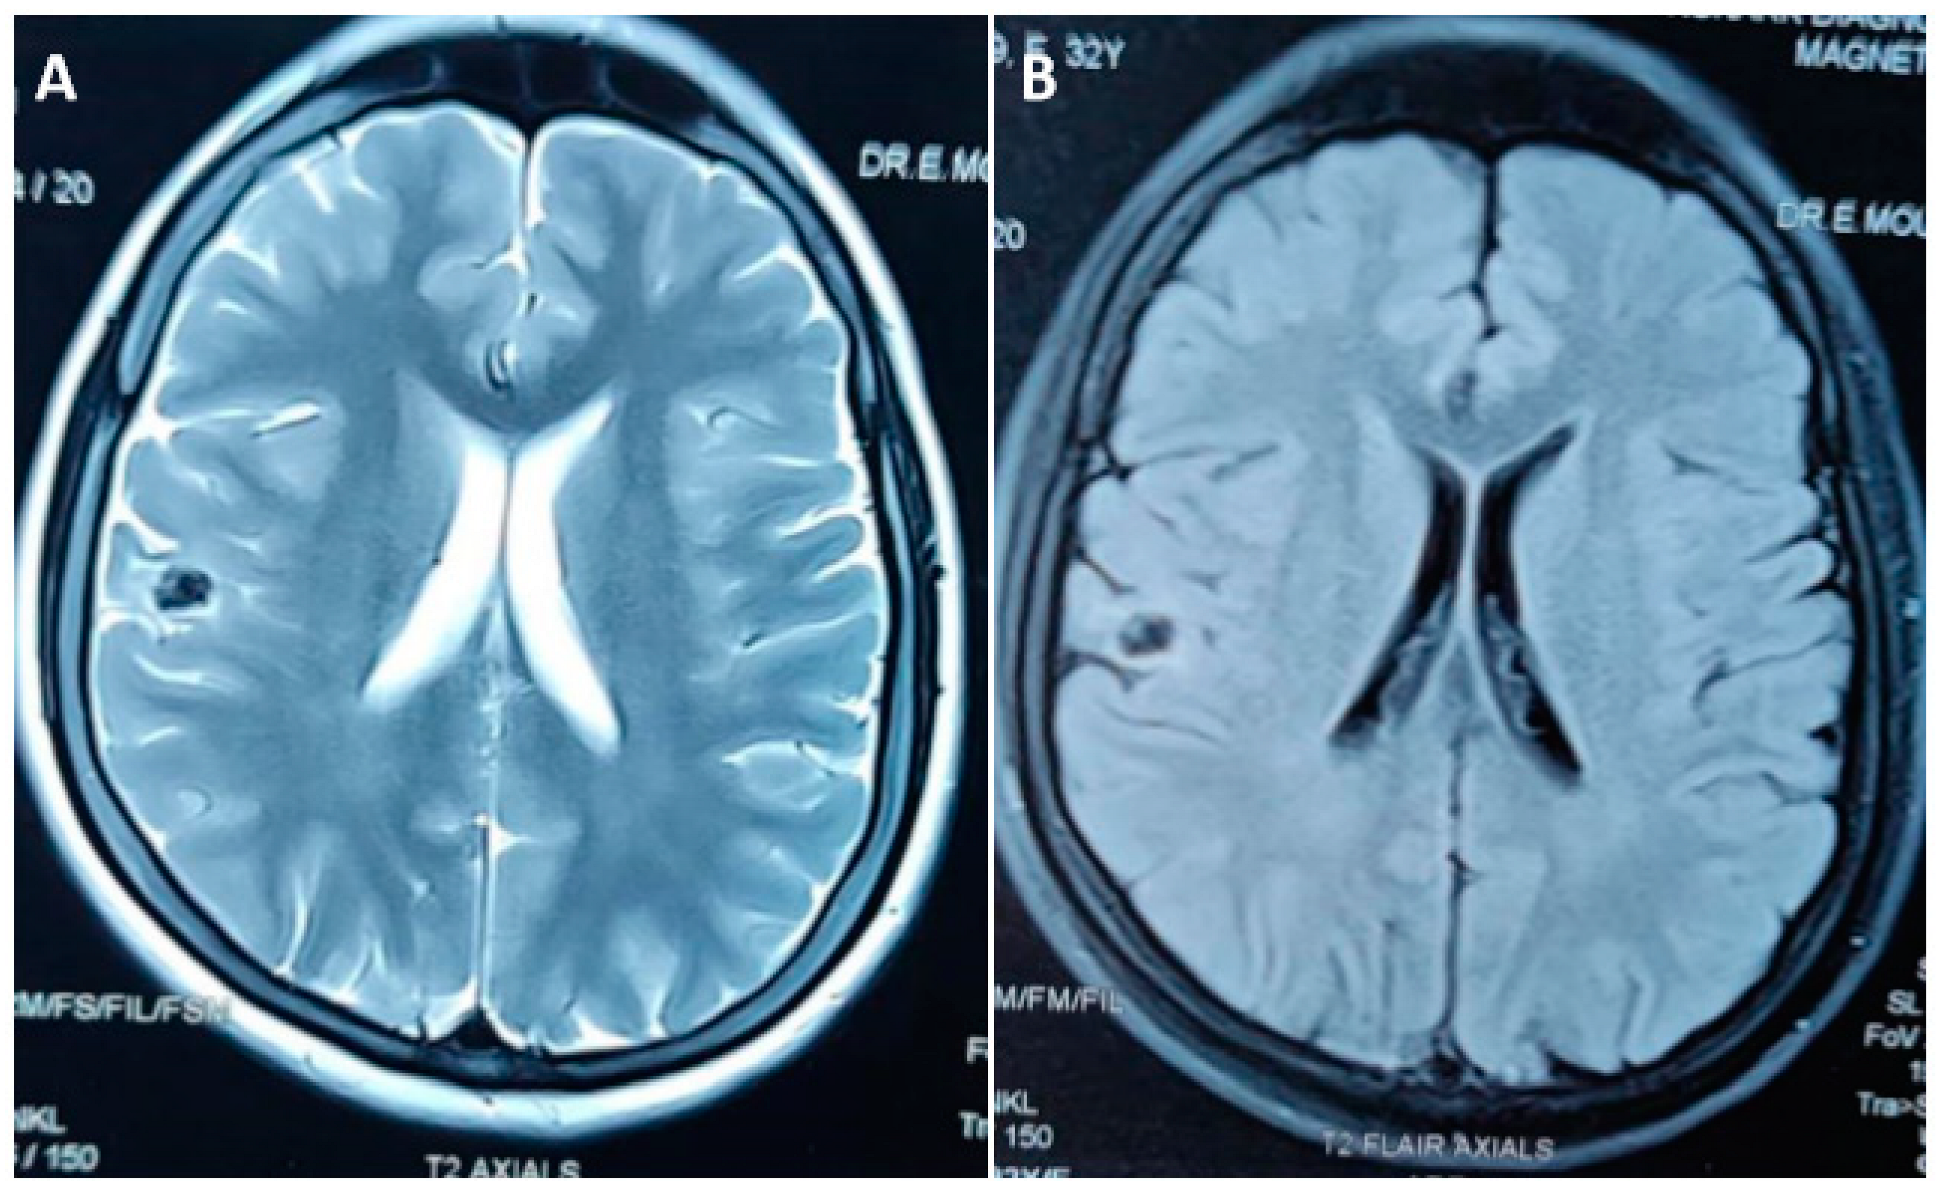

5. Calcified NCC: Epileptogenesis

- Jama-António, J.M.C.; Yasuda, C.L.; Cendes, F. Intermittent perilesional edema and contrast enhancement in epilepsy with calcified neurocysticercosis may help to identify the seizure focus. Epilepsia Open 2019, 4, 351–354. [Google Scholar] [CrossRef]

- Nash, T.E.; Pretell, E.J.; Lescano, A.G.; Bustos, J.A.; Gilman, R.H.; Gonzalez, A.E.; Garcia, H.H. Cysticercosis Working Group in Peru, Perilesional brain edema and seizure activity in patients with calcified neurocysticercosis. Lancet Neurol. 2008, 7, 1099–1105. [Google Scholar] [CrossRef] [PubMed]

- de Souza, A.; Nalini, A.; Kovoor, J.M.E.; Yeshraj, G.; Siddalingaiah, H.S.; Thennarasu, K. Perilesional gliosis around solitary cerebral parenchymal cysticerci and long-term seizure outcome: A prospective study using serial magnetization transfer imaging. Epilepsia 2011, 52, 1918–1927. [Google Scholar] [CrossRef]

- Nash, T.E.; Bartelt, L.A.; Korpe, P.S.; Lopes, B.; Houpt, E.R. Calcified neurocysticercus, perilesionaledema, and histologic inflammation. Am. J. Trop. Med. Hyg. 2014, 90, 318–321. [Google Scholar] [CrossRef]

- Ooi, W.W.; Wijemanne, S.; Thomas, C.B.; Quezado, M.; Brown, C.R.; Nash, T.E. Short report: A calcified Taenia solium granuloma associated with recurrent perilesional edema causing refractory seizures: Histopathological features. Am. J. Trop. Med. Hyg. 2011, 85, 460–463. [Google Scholar] [CrossRef]

- Rathore, C.; Thomas, B.; Kesavadas, C.; Abraham, M.; Radhakrishnan, K. Calcified neurocysticercosis lesions and antiepileptic drug resistant epilepsy: A surgically remediable syndrome? Epilepsia 2013, 54, 1815–1822. [Google Scholar] [CrossRef]

- Gupta, R.K.; Kumar, R.; Chawla, S.; Pradhan, S. Demonstration of Scolex within Calcified Cysticercus Cyst: Its Possible Role in the Pathogenesis of Perilesional Edema. Epilepsia 2002, 43, 1502–1508. [Google Scholar] [CrossRef]